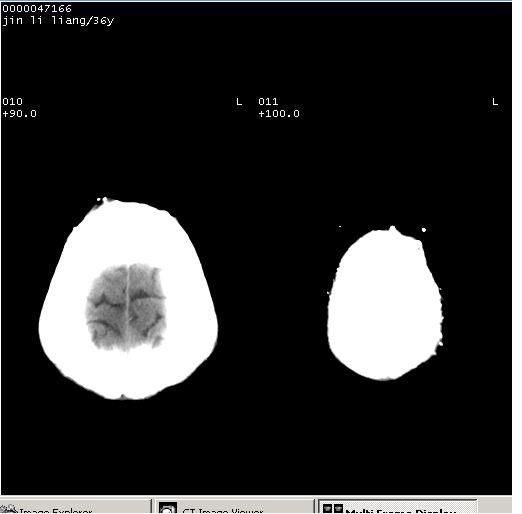

患者 男,36岁。头面部“土炮”炸伤。pe:面目全非,伤口流血不止。

临床诊断:头面部外伤。

颅脑ct轴位平扫(层厚、层距均为10mm),图像如下:

左眼球破裂并异物,眶周、额顶部头皮及软组织挫伤并异物

迎面一炮,满脸开曝。额顶部头皮及软组织挫伤并异物,左眼球破裂积气并异物,典型的面目全非,惨不忍睹。

左眼球破裂积气并异物,眶周、额顶部头皮及软组织挫伤并异物,右侧眼环前内分异物

1左侧眼球破裂并积气,球内、框内异物。

2额部顶部软组织伤。